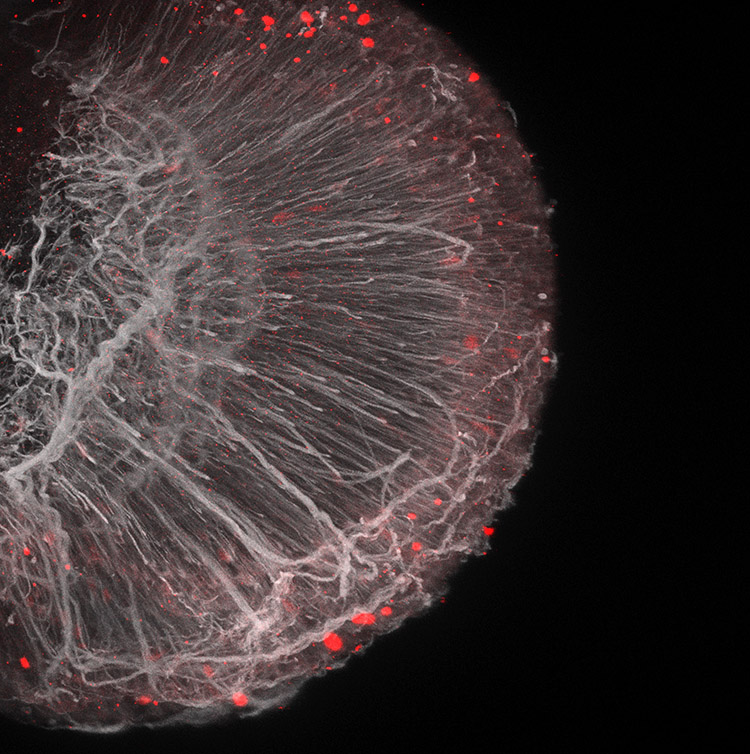

Tissue engineering and regenerative ophthalmology is a field that has been making remarkable strides in recent years, revolutionizing the way we treat eye diseases and injuries. Using cutting-edge technologies and innovative approaches, researchers in this field are developing advanced materials, biocompatible scaffolds, and bioactive molecules that can help restore vision and repair damaged eye tissues. From corneal transplants and retinal implants to stem cell therapies and gene editing, the possibilities in tissue engineering and regenerative ophthalmology are truly awe-inspiring. With its potential to improve the quality of life for millions of people worldwide, it's no wonder that this field is considered one of the coolest and most exciting areas of research today.

Regenerative Cellular Therapies

Stem Cell Derived Retinal Organoids